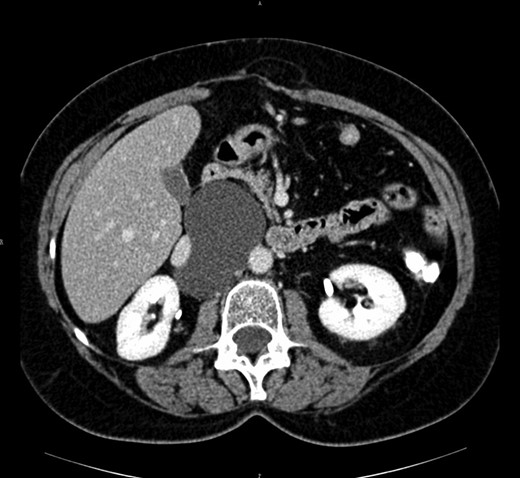

The abdominal computed tomography scan with contrast revealed a huge (10 cm of diameter) retroperitoneal cyst, oval shaped and containing dense fluid, located within the caval vein and the aorta, under the origin of the renal artery, partially dislocating the caval vein to the right (see Fig. 2).

Computed tomography view of the mesenteric cyst partially dislocating the caval vein.